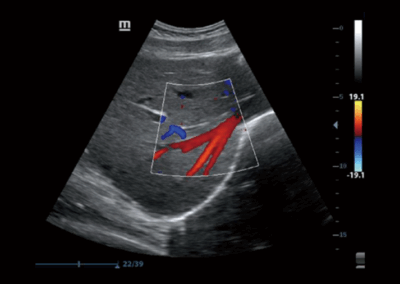

Z50

Sistema de diagnóstico ecográfico.

Con la combinación definitiva de alto rendimiento, aplicaciones clínicas integrales y diseño integrado, el Z50 lo ayudará a responder de manera más rápida y eficaz. El cambio de un sistema en blanco y negro a un sistema Doppler a color altamente eficiente ahora se ha vuelto más fácil y simple que nunca, lo que hace posible ir más allá de los límites y trascender lo habitual cuando se trata de la atención de los pacientes.